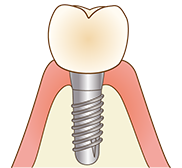

当院のインプラントは、40年以上の歴史があるノーベルバイオケア社(スイス)を使用しており、骨との親和性に優れる「純チタン」の表面に「タイユナイト」と呼ばれる表面加工が施されており、周囲の骨形成が促進されると言われています。

世界中の歯科医院でも広く使われているため、引越しなどの理由で当院に通えなくなってしまった場合も、メインテナンスを受けることができます。